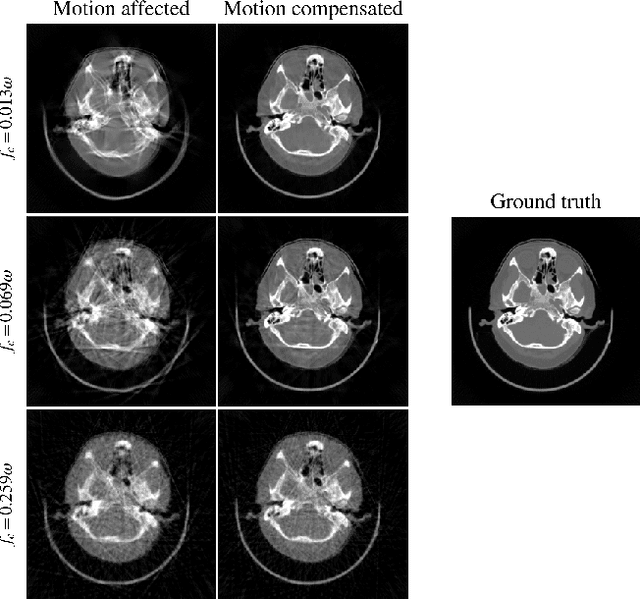

Abstract:Computed tomography (CT) relies on precise patient immobilization during image acquisition. Nevertheless, motion artifacts in the reconstructed images can persist. Motion compensation methods aim to correct such artifacts post-acquisition, often incorporating temporal smoothness constraints on the estimated motion patterns. This study analyzes the influence of a spline-based motion model within an existing rigid motion compensation algorithm for cone-beam CT on the recoverable motion frequencies. Results demonstrate that the choice of motion model crucially influences recoverable frequencies. The optimization-based motion compensation algorithm is able to accurately fit the spline nodes for frequencies almost up to the node-dependent theoretical limit according to the Nyquist-Shannon theorem. Notably, a higher node count does not compromise reconstruction performance for slow motion patterns, but can extend the range of recoverable high frequencies for the investigated algorithm. Eventually, the optimal motion model is dependent on the imaged anatomy, clinical use case, and scanning protocol and should be tailored carefully to the expected motion frequency spectrum to ensure accurate motion compensation.